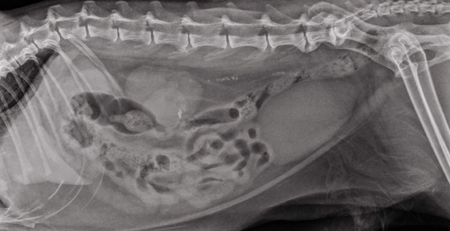

Claves para la colocación de una cánula ureteral: estudio de un caso

De un 2% a 4% de la población de mascotas a nivel mundial tiene o ha tenido cálculos.